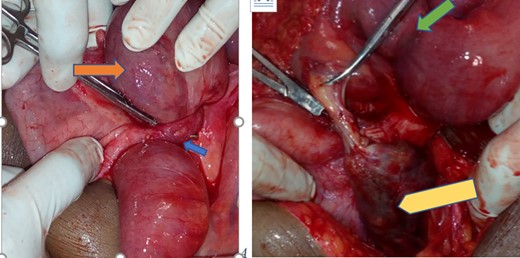

With the diagnosis SBO secondary to adhesion band, the patient was taken to the operation room after and the finding was dilated small bowel loops with closed loop obstruction at distal 8 cm of ilium by appendicular knot. At the tip of the appendix there is 4×2 cm cystic mass with no solid component. Retrograde appendectomy including mesoappenix done (Fig. 2). The biopsy result is mucions cyst adenoma with no extension in the surrounding mesoapppendix and the base of the appendix. (Fig. 3) There was a pressure mark exactly at the ileocecal junction and 8 cm away from it. Post-operatively, the patient started sips on second day discharged on fifth day with post-operative diagnosis of SBO secondary to appendico-ilial knotting with appendicular mucocele.

Appendix with mucocele entangling distal ilium forming closed loop obstruction (blue arrow—appendicular knot, orange—entangled distal ilium, green—the pressure mark on the distal ilium and yellow—gangrenous appendicular mucocele).